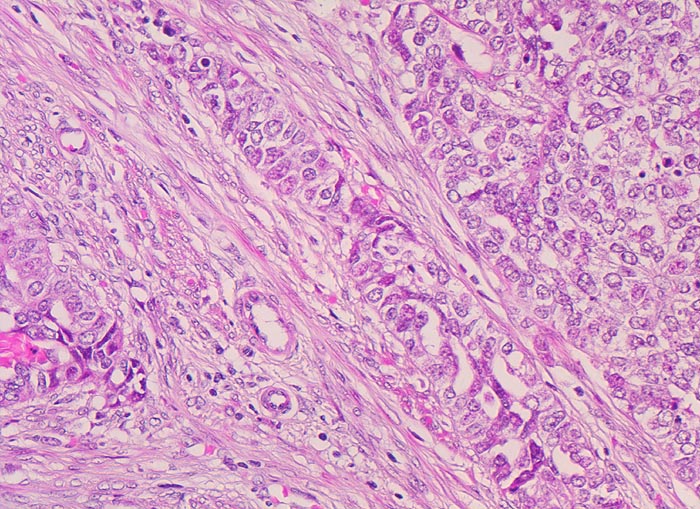

endometrioides Adenokarzinom: Invasion des Myometrium

Solide Tumorzellverbände infiltrieren die glatte Muskulatur des Myometrium. Die Tumorzellen haben grosse runde vesikuläre Kerne und wenig Zytoplasma.

Exophytischer, in das Uteruscavum hineinragender, weicher fokal hämorrhagischer Tumor ausgehend von der Uterushinterwand. Das Tumorgewebe infiltriert die innere Hälfte des Endometriums.